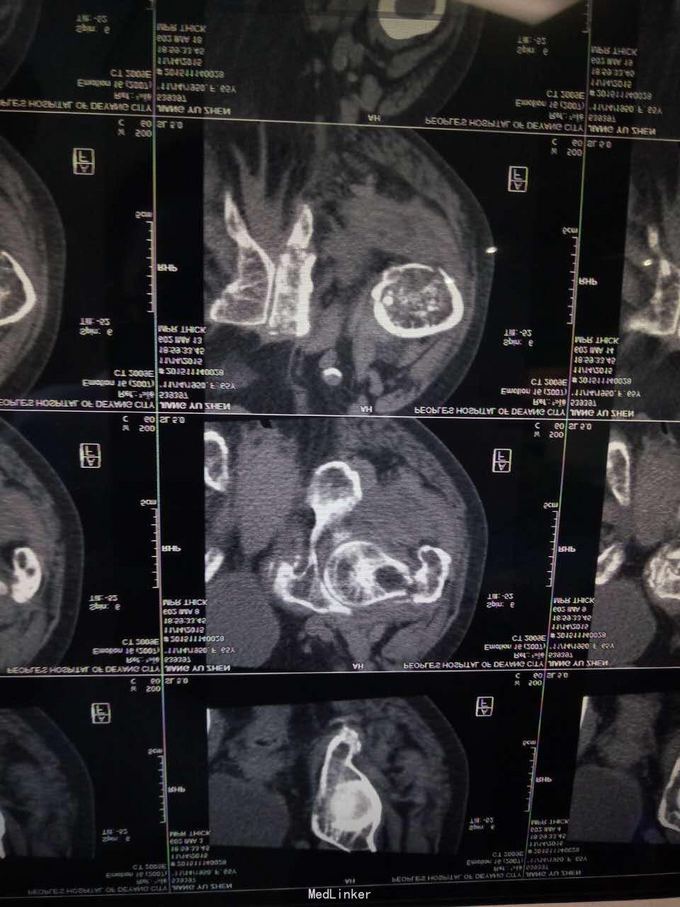

查体,左下肢外旋畸形,髋部压痛,轴向叩击痛。 x片提示:左股骨颈、转子间骨折,左股骨耻骨上支,耻骨联合、下肢粉碎性骨折。

诊断:左股骨颈、转子间粉碎性骨折,左耻骨上支、耻骨联合、下支粉碎性骨折,重度骨质疏松症, 处理:患肢制动,牵引,注射鲑降钙素,科室讨论意见为行髋关节置换术,与换方沟通后,换方表示拒绝手术治疗,主动出院。